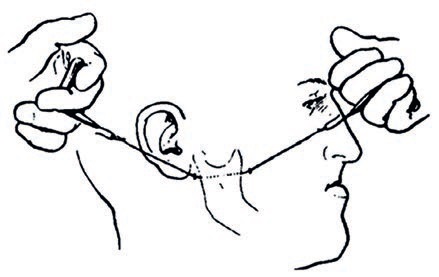

Łączne leczenie ortodontyczne i chirurgiczne ciężkiej wady zgryzu klasy III ze zgryzem krzyżowym przednim i tylnym

60 lat innowacji w biomechanicznej chirurgii ortognatycznej: stan wiedzy i kierunki na przyszłość